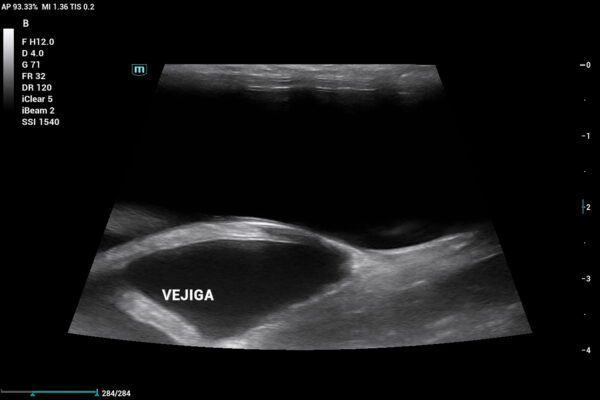

Existe una larga lista de problemas asociados a la no esterilización en conejas. Los primeros a los que nos podemos enfrentar son: neoplasias (habitualmente adenocarcinomas), hiperplasia endometrial (con o sin formación quística), piometra, hidrómetra (imágenes 1 y 2) o mucómetra, aneurismas venosos endometriales, pseudogestación y problemas digestivos secundarios derivados del malestar, el dolor y la no ingestión de cecotrofos, con todo lo que esto conlleva.

Se realiza ecografía abdominal, que evidencia que aún cuenta con cuernos uterinos (imagen 6), lo que confirma la ovariectomía (no ovariohisterectomía). Por este motivo, se decide enviar una muestra de plasma sanguíneo a un laboratorio externo para evaluar los niveles de 17β-estradiol, dado que en ecografía no se logra distinguir con claridad un remanente ovárico.